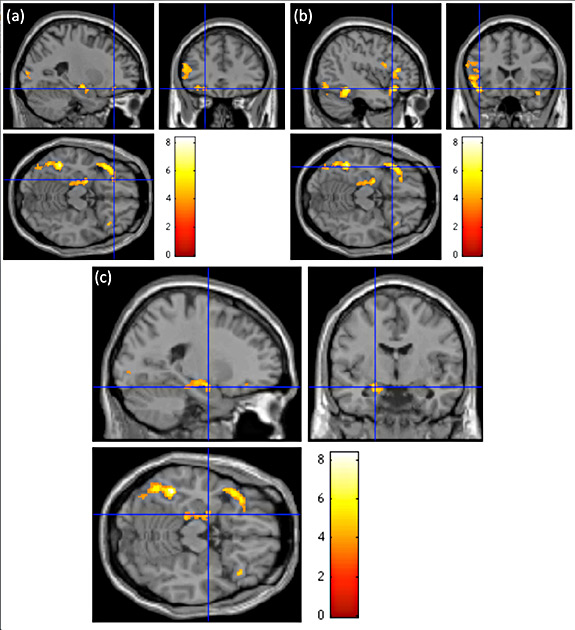

Sentences containing words that invoked taste activated areas in the lateral orbitofrontal cortex (a) and frontal operculum (b) known as the gustatory cortices that allow for the physical act of tasting. Taste-related metaphors also stimulated brain regions known to be associated with emotional processing, such as the left hippocampus, parahippocampal gyrun and amygdala (c). The colors indicate the level of activation prompted by metaphorical sentences in comparison to literal sentences with 8 signifying the greatest amount of neural activity. Image courtesy of Adele Goldberg, Council of the Humanities

The researchers found that the sentences containing words that invoked taste activated areas known to be associated with emotional processing, such as the amygdala, as well as the areas known as the gustatory cortices that allow for the physical act of tasting. Interestingly, the metaphorical and literal words only resulted in brain activity related to emotion when part of a sentence, but stimulated the gustatory cortices both in sentences and as stand-alone words.